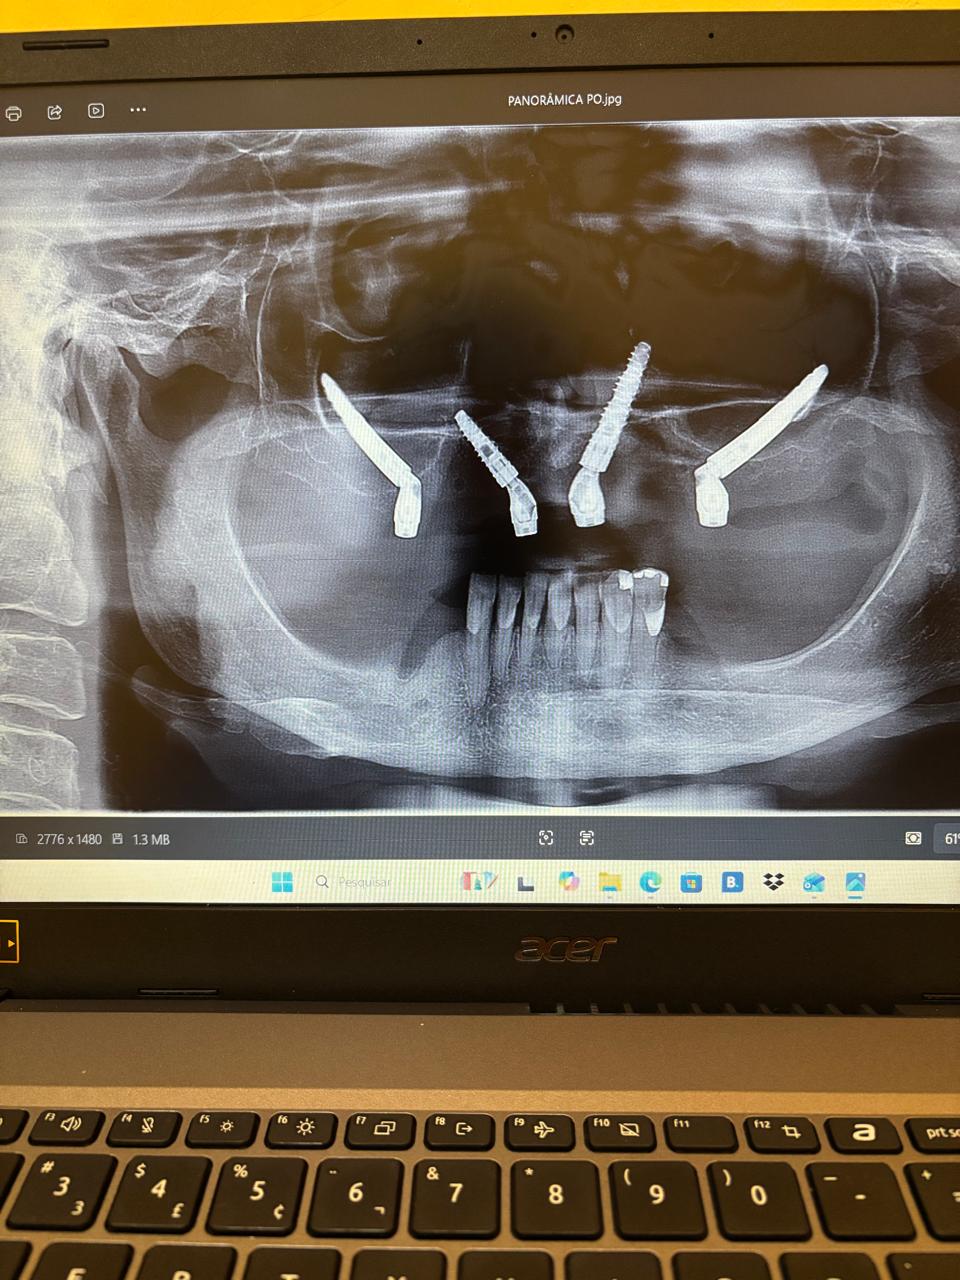

Realizamos cirurgias bucomaxilofaciais e implantes com atenção personalizada para cada paciente.

Implantes dentários instalados